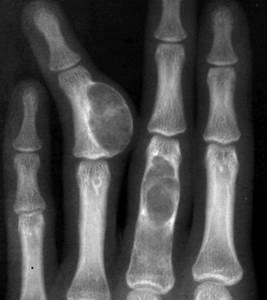

1、X射线检查:X射线检查是很常用的骨骼检查方法,当骨骼被癌肿破坏一厘米以上且骨骼脱钙达到一半多之时,X射线平片才能观察到局限性的骨密度减低、骨小梁模糊或消失等现象。如果癌肿已侵犯到了周围的软骨组织,X射线平片可观察到局部软组织的块影现象。

2、CT检查:CT检查可观察到患者肿瘤对骨骼的破坏程度,如肺、肾和胃肠道的恶性肿瘤转移至骨骼时可引起溶骨性的骨改变。而来源于乳腺和前列腺的恶性肿瘤发生骨转移时,多是引起成骨性的骨改变。